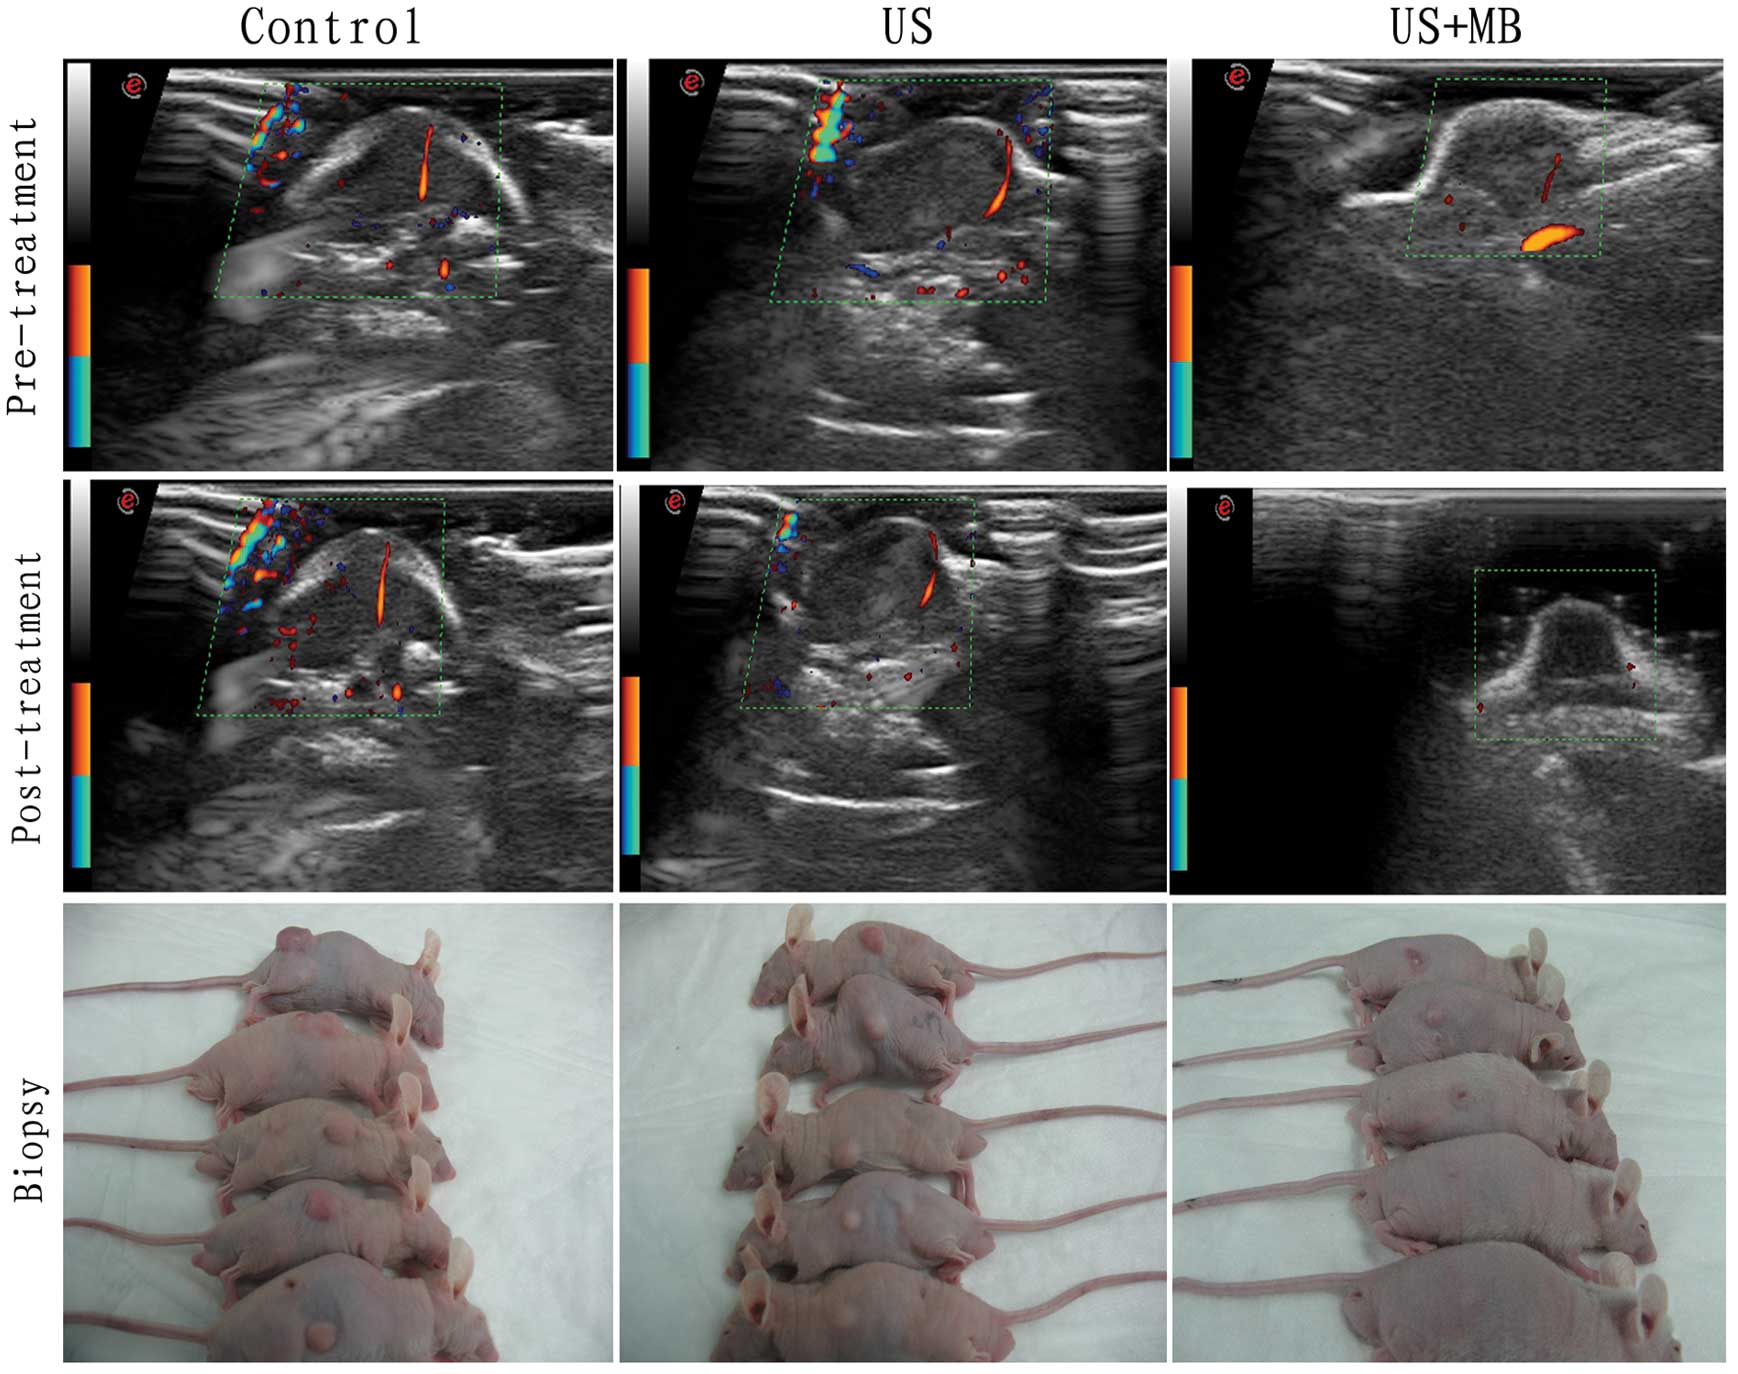

Prior to the treatment, CDFI demonstrated a blood flow signal within all the tumors of the three groups. In the US+MB group only, the blood flow signal disappeared following 2 weeks of treatment, while in the control and US group, the flow signal in the tumors remained (Fig. 2).

Figure 2

CDFI prior to and following treatment in the control, US and the US+MB group. Following 2 weeks of treatment, the blood flow signal in the US+MB group disappeared, and the tumor size was smaller when compared with the other 2 groups. CDFI, color Doppler flow imaging; US, ultrasound; MB, microbubble.

Tumor size calculation

The tumor size of the three groups is manifested in Figs. 2 and 3. There were significant differences in tumor size among the three groups, as determined using the ANOVA test; F=8.418 and P=0.0052. There was a significant difference between the US+MB group and the control and US groups, with t=3.804 and P=0.0052, and t=3.117 and P=0.0143, respectively (Figs. 2 and 3).